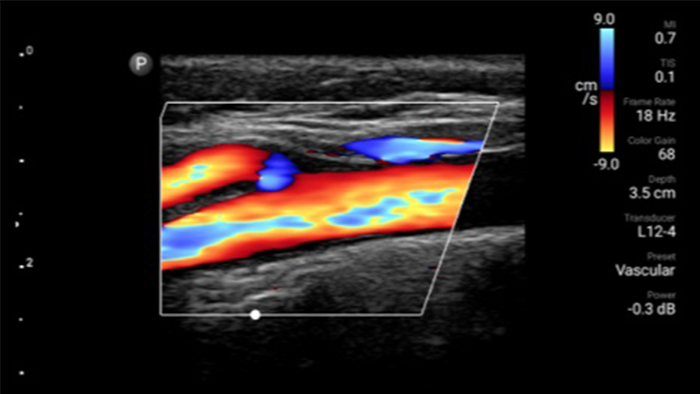

Exceptional ultrasound imaging

Lumify handheld ultrasound offers images that enhance diagnostic confidence.